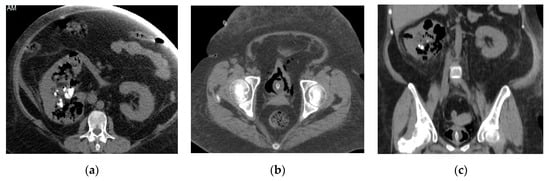

2.6. Emphysematous Urinary Tract Infection

| Emphysematous UTIs | Gas in the renal parenchyma, collecting system, bladder lumen and sometimes in the perirenal and perivesical tissue. |